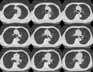

¥ Lung Cancer: Adenocarcinoma

8mmx4, Pitch 6, 384mm, 4-seconds, 150-mAs:

"High-speed screening mode."